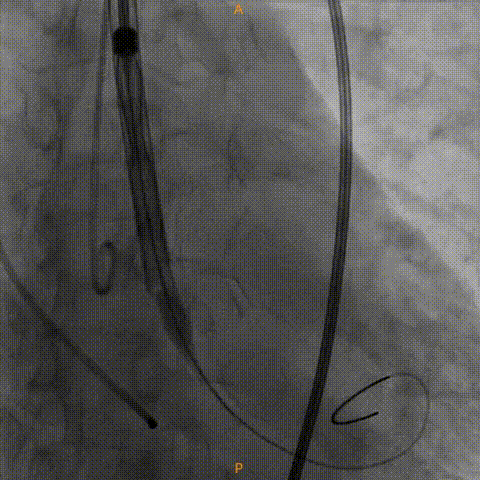

手术影像:

主动脉根部造影

工作位造影